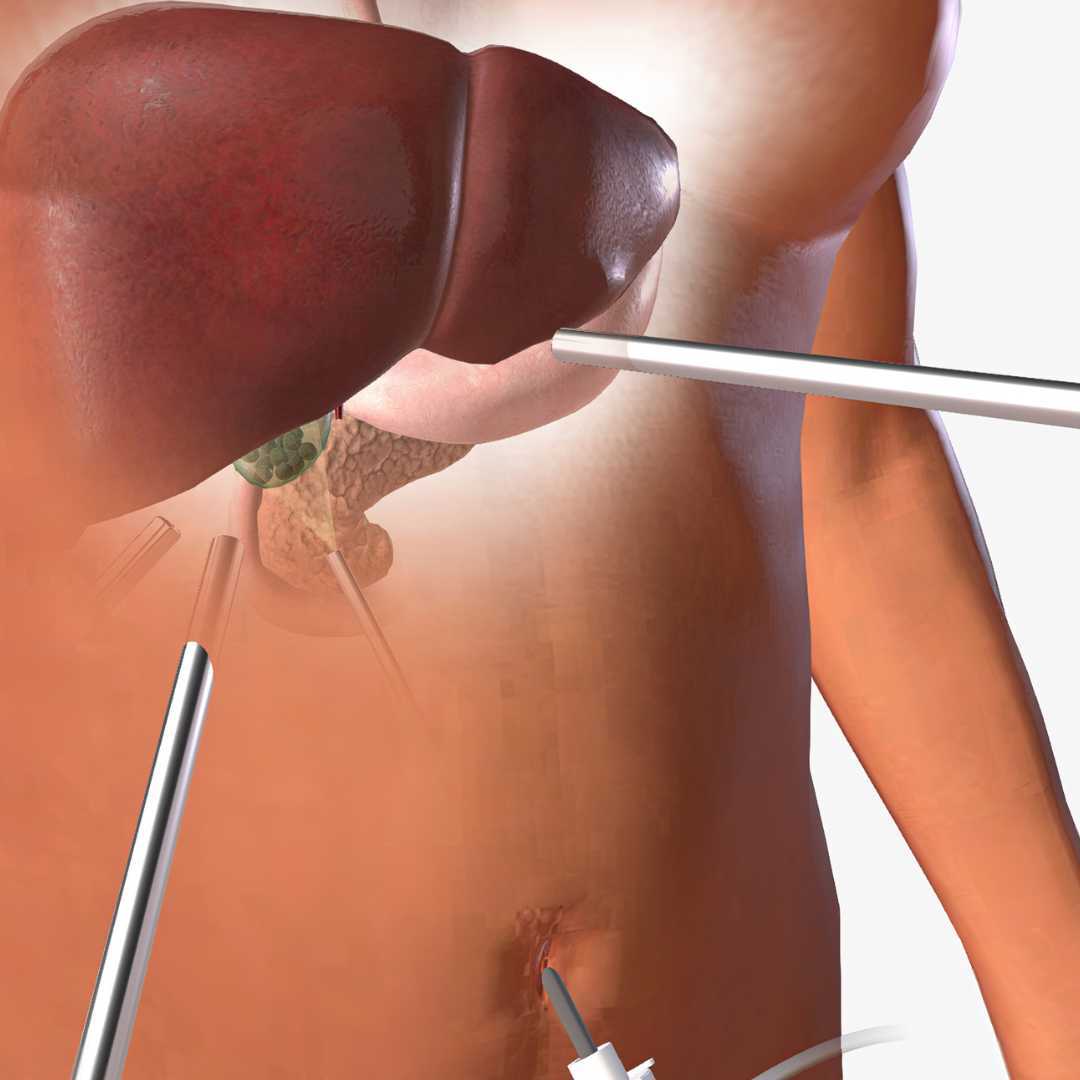

A hiatal hernia is generally located in the stomach area or the esophagus, the swallowing tube that connects the mouth to the stomach. This tube passes through the diaphragm, and often grows too wide, causing acids and foods from the stomach to regurgitate back up into the tube. Hiatal or hiatus is the medical name for an opening or tear. Therefore, a hiatal hernia often occurs if a small portion of the stomach is pushed up through that opening, causing symptoms such as heartburn and chest pain as well as acid reflux. A variety of treatments for hiatal hernia repair are available, including laparoscopic surgery.

Piedras Negras in Mexico is a popular location for hiatal hernia treatments at reputed medical centers. The expert medical professionals utilize laparoscopic surgery to treat the syndrome effectively with fast healing and recovery.